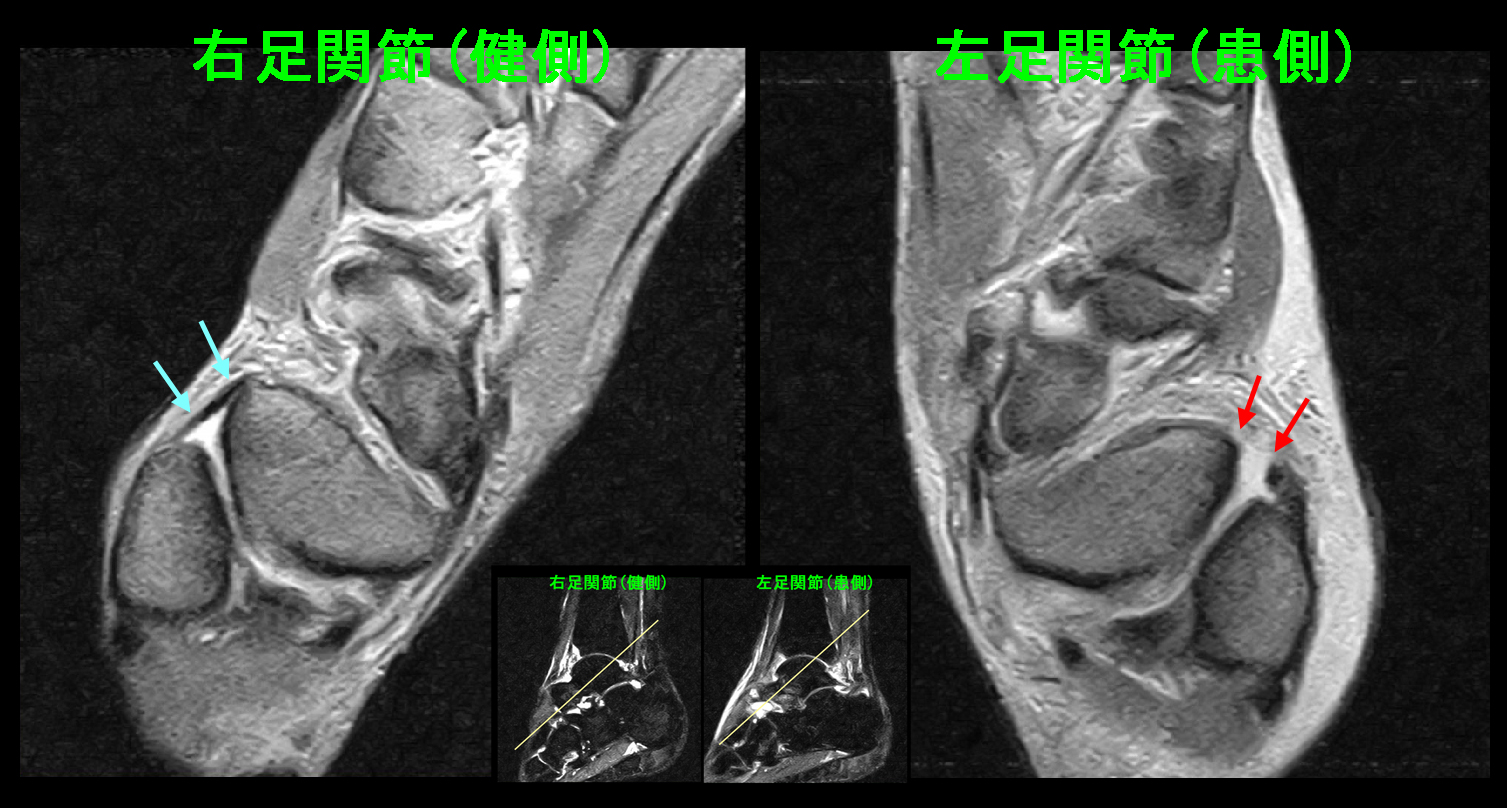

14才女 MR1.jpg

MRI検査(骨が黒く見えるSTIRという条件)では患側の右足関節には骨の損傷はなく、関節部の白さが広がっており(赤矢印)、関節内に出血を認める関節炎の所見です。健側の左足関節の距骨の後ろ側が軽度高輝度を示しており、こちらはケガしていないのですから、元々の運動による痛みを伴っていない疲労骨折の前駆状態と理解されます。このようなことはしばしば見られるものです。

14才女 MR2.jpg

バレーボールの男子生徒のように足関節を斜めに切るMRI所見(GR条件)では前距腓靭帯が断裂しています(赤矢印)。この状態で全力で走れるようになるには最低で4週間ぐらいはかかるものです。しかし、本人は大会に出たいはずで、私は関節内注入療法をすれば出場できるかもしれないと提案しました。本人も同意して関節内注入を行い、簡易タイプのギプスシーネ固定を行い、投薬は10日分処方し大会終了まで服薬を継続し、3日間固定した後にシーネを外して練習を開始してみる治療方針としました。